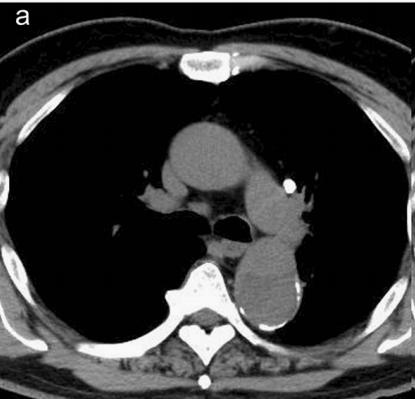

病例8

查到一篇文献,作者虽然用箭头标记了,并且是增强CT,但是鲁迅说:我大约肯定没有看出来,这是主动脉夹层!

图21